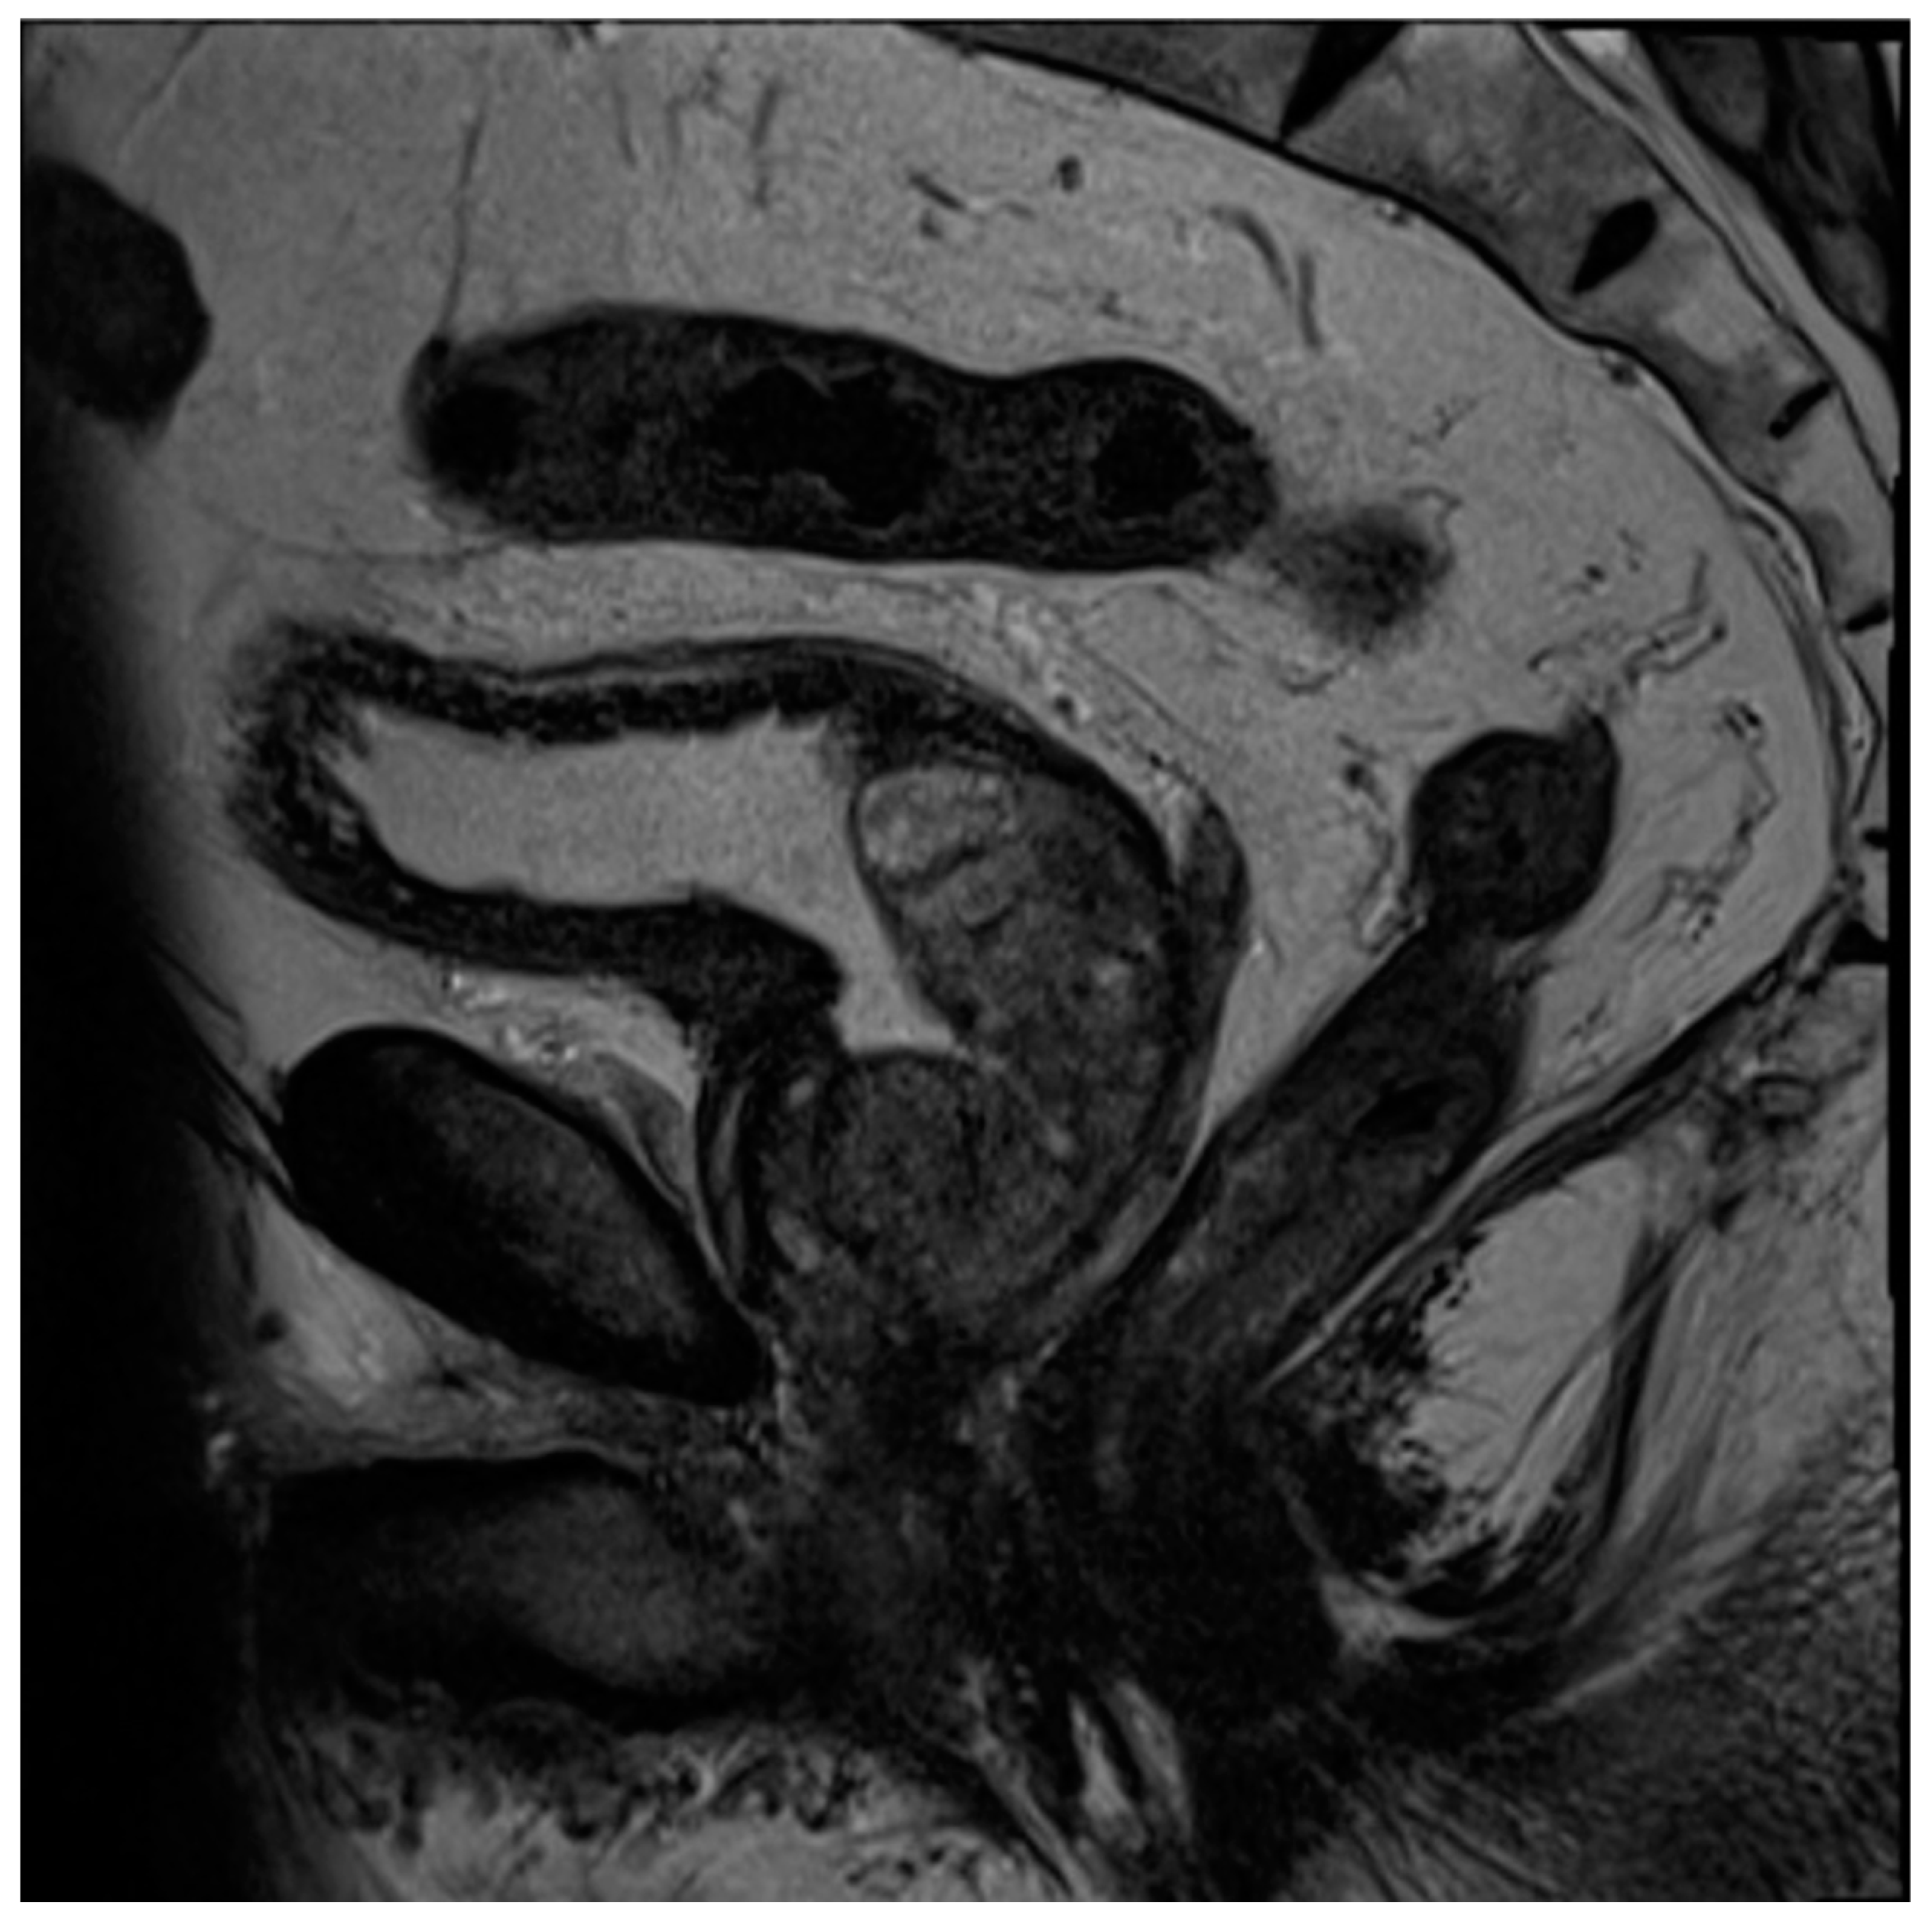

To briefly summarize the system, PI-RADS uses a grading scale from 1 to 5, wherein benign-appearing lesions receive a score of 1, and highly suspicious lesions are given a score of 5. The peripheral zone of the prostate is primarily assessed using diffusion-weighted sequences (DWI/ADC), where more convincing diffusion restriction is considered increasingly suspicious. In contrast, the transition zone is primarily assessed using T2-weighted sequences, where hypointense lesions are considered more suspicious as they become less circumscribed, homogenous, and with obscured margins, leading to suspicious lesions often being likened to “smudged charcoal” [28]. In both peripheral and transition zone lesions, maximal lesion diameter determines if a suspicious lesion is categorized as 4 or 5. DCE only impacts the overall scoring of a lesion in situations where a positive DCE can upgrade a peripheral zone lesion from 3 to 4. PI-RARDS v2.1 clarifies that DCE is considered negative if enhancement is diffuse, multifocal, does not correlate to a T2 or DWI abnormality, or if it does correspond to lesions compatible with BPH (Figure 2) [27]. While PI-RADS is also used during the setting of active surveillance, the Prostate Cancer Radiological Estimation of Change in Sequential Evaluation (PRECISE) score has also been developed to help standardize reporting of active surveillance cases and better stratify those who need or can avoid surveillance biopsy [45]. The PRECISE score is based on a 5-point scale where a score of 1 indicates the resolution of suspicious MRI features, 2 indicates a reduction in volume/conspicuity of MRI features, 3 indicates a stable MRI appearance, and scores of 4 and 5 demonstrate a significant increase in volume/conspicuity and/or definite stage progression [45]. Using this standardized approach, this initial study found that PRECISE scores of 1–3 have high NPV and can reduce the need for re-biopsy during active surveillance, while scores of 4–5 have moderate PPV and should be closely monitored or biopsied [45].

Figure 2. Axial T2 (A), diffusion-weighted b2000 (B), apparent diffusion coefficient (C), and dynamic contrast-enhanced (D) images of the pelvis demonstrating a focal ill-defined T2 hypointense lesion in the right midgland posterolateral peripheral zone with corresponding diffusion restriction and asymmetric enhancement, characterized as PI-RADS 5 per PI-RADS v2.1.